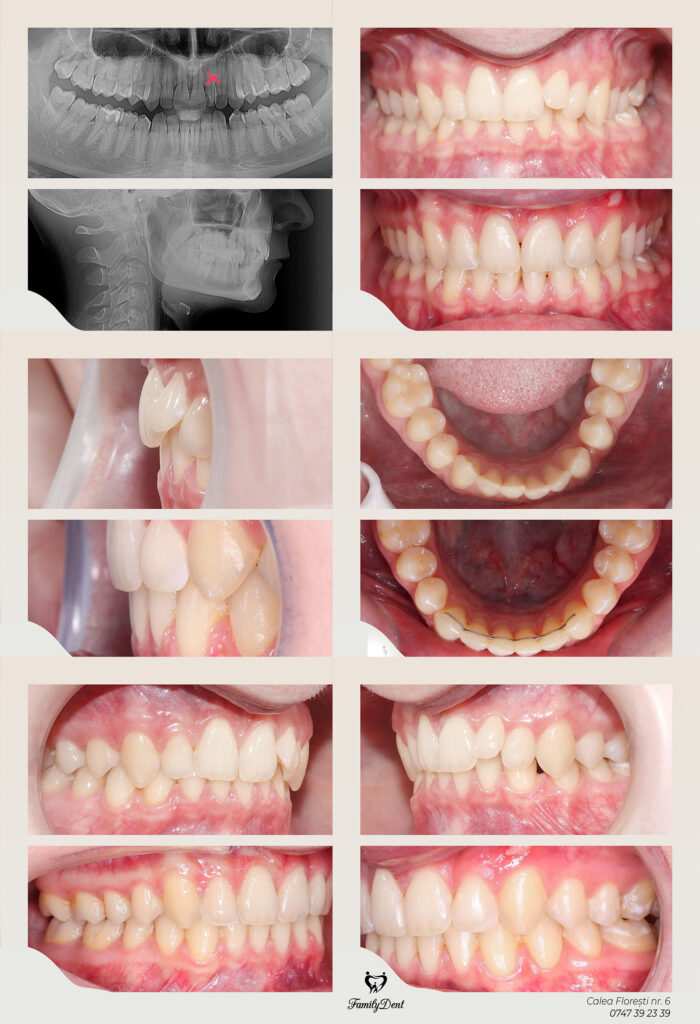

Caz ortodontic complex, pe care am reușit să-l tratăm fără chirurgie ortognată. Acest tratament a fost propus pacientei și la alte cabinete, dar fost un refuz categoric din partea acesteia.

Astfel, cu ajutorul aparatului ortodontic fix am reușit corectarea mușcăturii încrucișate pe partea stângă și închiderea tututor spațiilor, fără ca pacienta să fie nevoită ulterior să recurgă la inserarea implaturilor dentare.